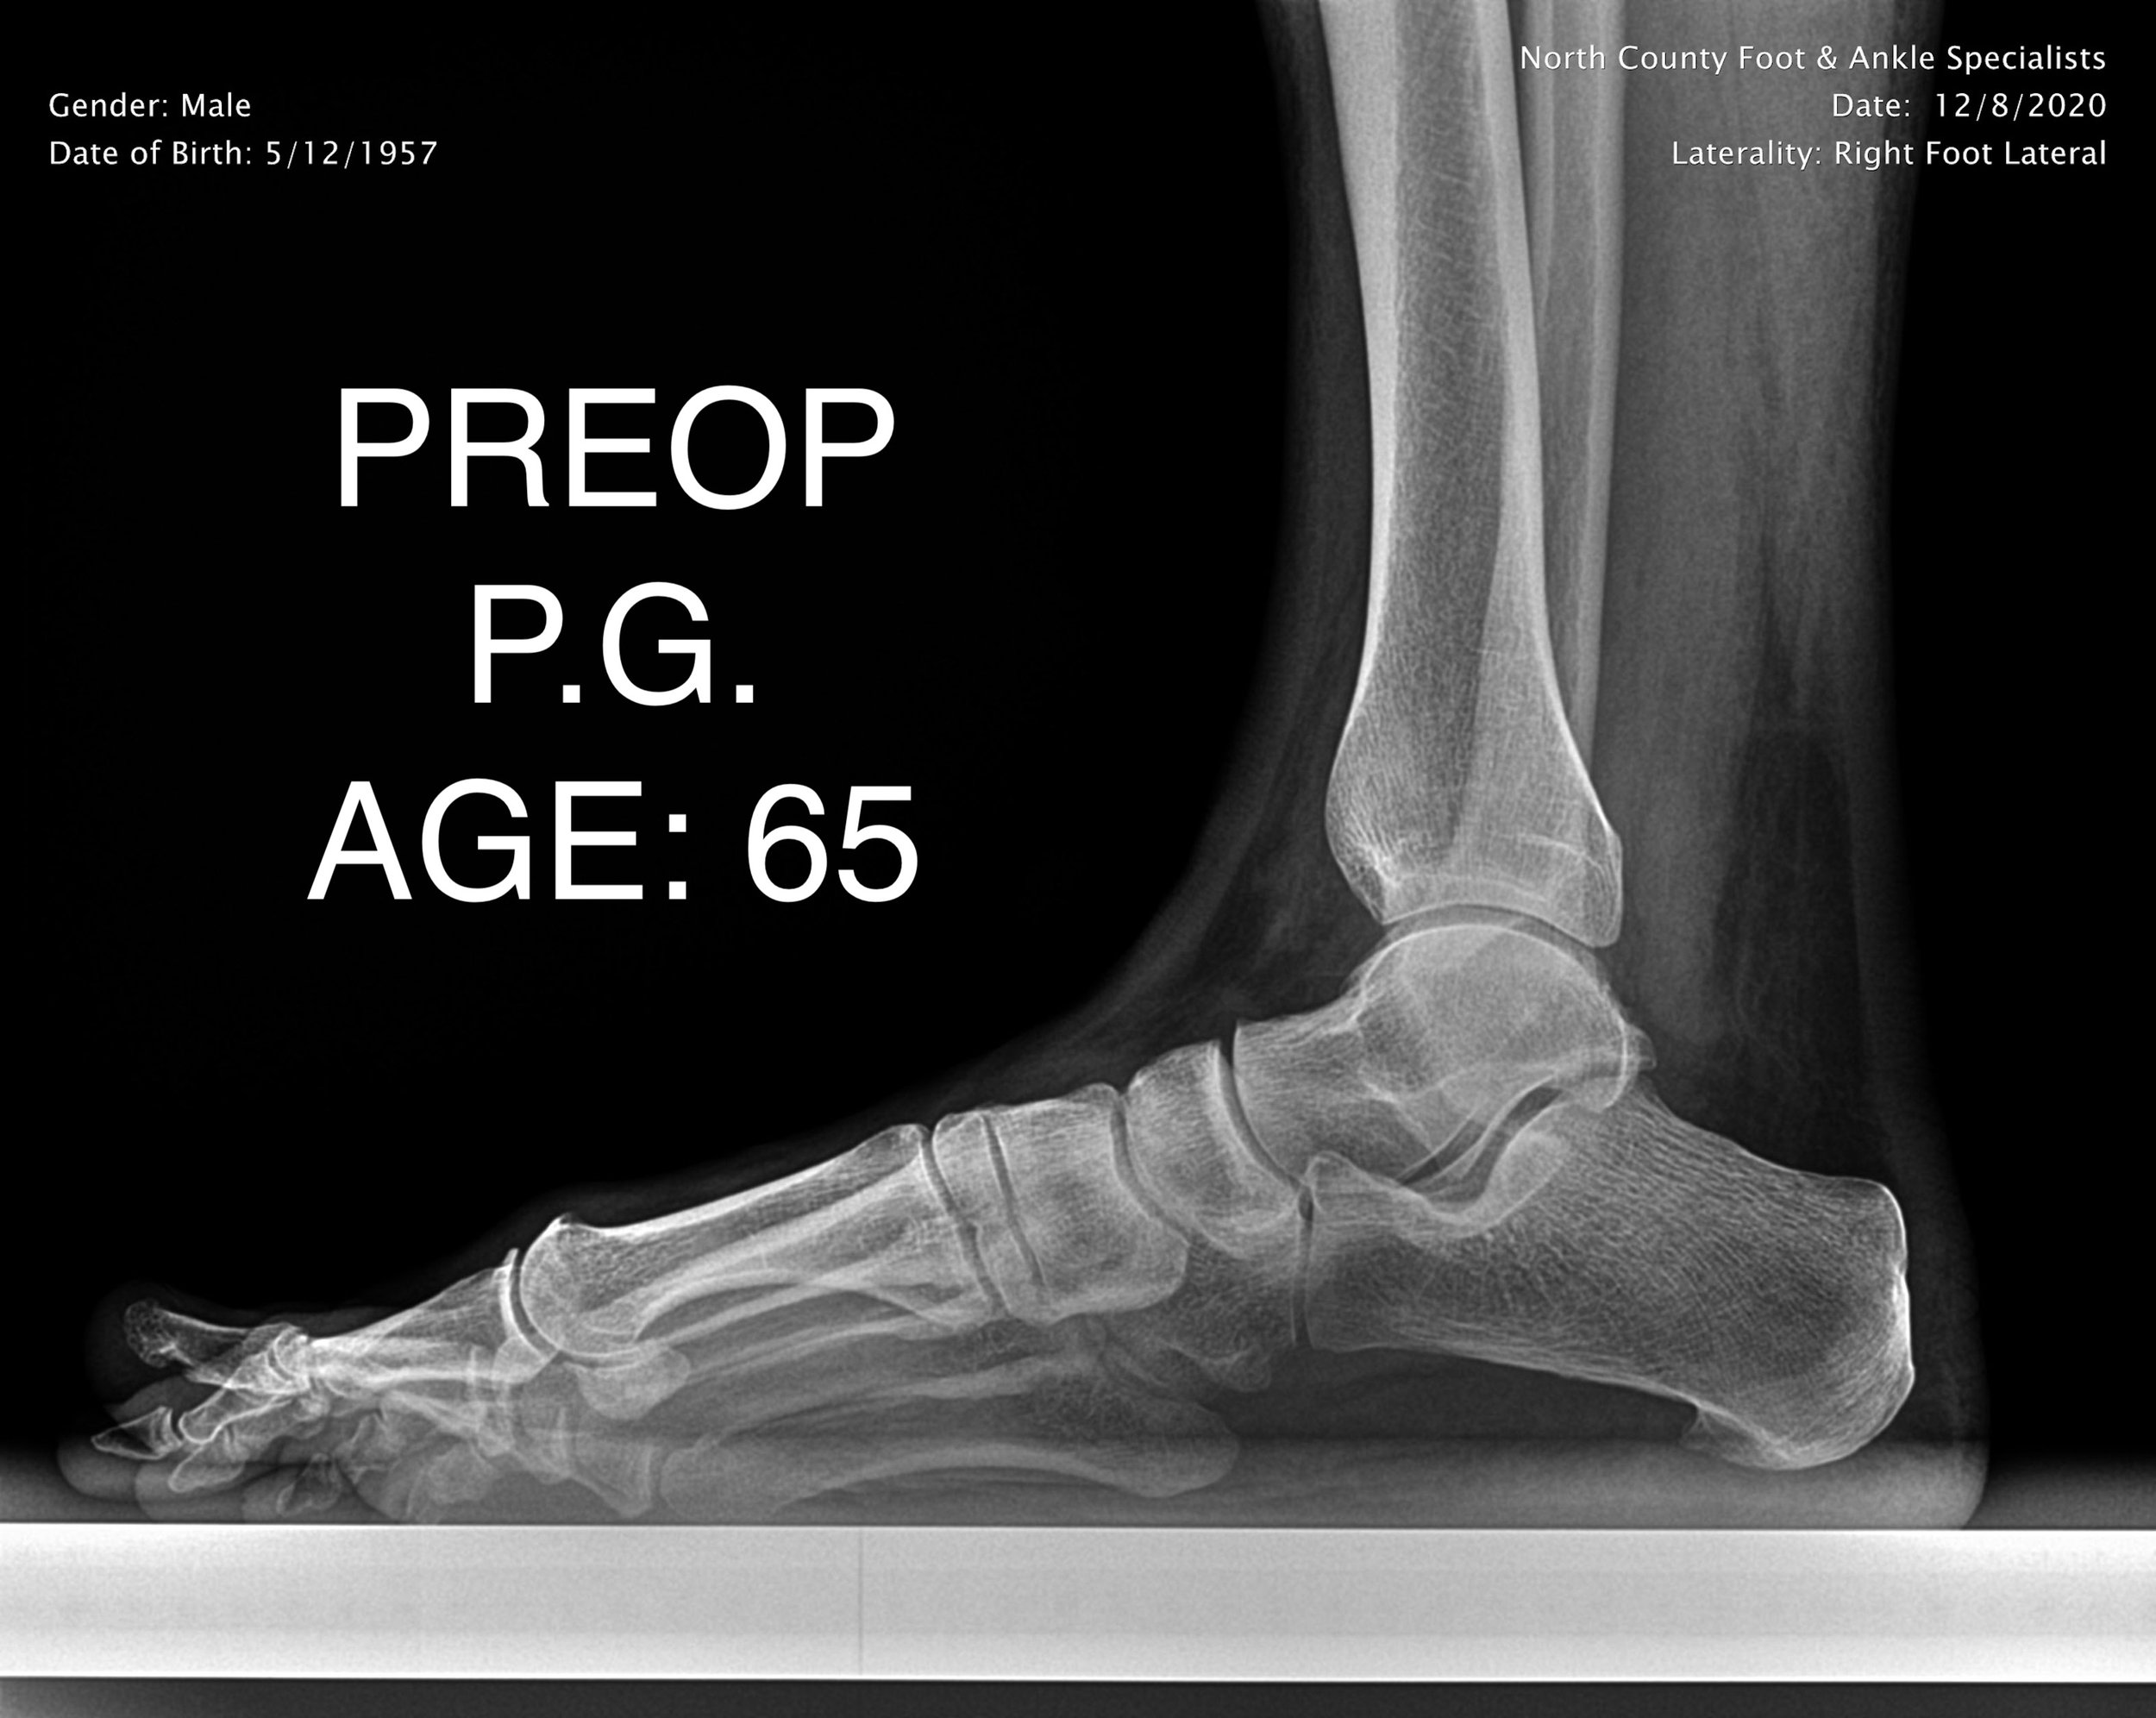

ADULT FLAT FOOT RECON